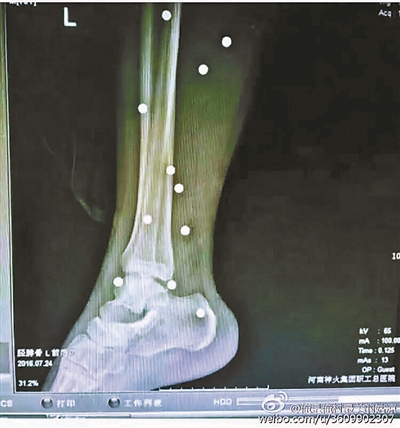

傷者體內(nèi)取出的鋼珠

爆炸導(dǎo)致鋼珠遍布傷者身體各處

黃明的伯伯對北青報(bào)記者表示,由于黃明直接踩到了爆炸物,所以傷情最為嚴(yán)重,“他的腿被炸斷,身體內(nèi)被炸進(jìn)了40多顆鋼珠。手術(shù)后已經(jīng)從體內(nèi)取出29顆鋼珠,還有十多顆鋼珠沒有取出來?!备鶕?jù)黃明的入院記錄,他全身有多處爆炸傷,且全身多處異物存留。

爆炸發(fā)生時,陳浩的位置與黃明靠得很近,因此也受傷較重。他告訴北青報(bào)記者,經(jīng)過10多個小時的手術(shù)后,醫(yī)生從他身體里取出了12顆鋼珠。目前,他和黃明兩人經(jīng)過手術(shù)后,已從重癥監(jiān)護(hù)室轉(zhuǎn)至普通病房。其余三人中,陳剛的臀部受傷,當(dāng)天晚上在醫(yī)院清理完傷口后便回了家,而同行的兩名女生身上有一些擦傷。